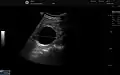

![]() | |

| Renal cyst of the left kidney (hyperintense area) as shown on MRI. | |